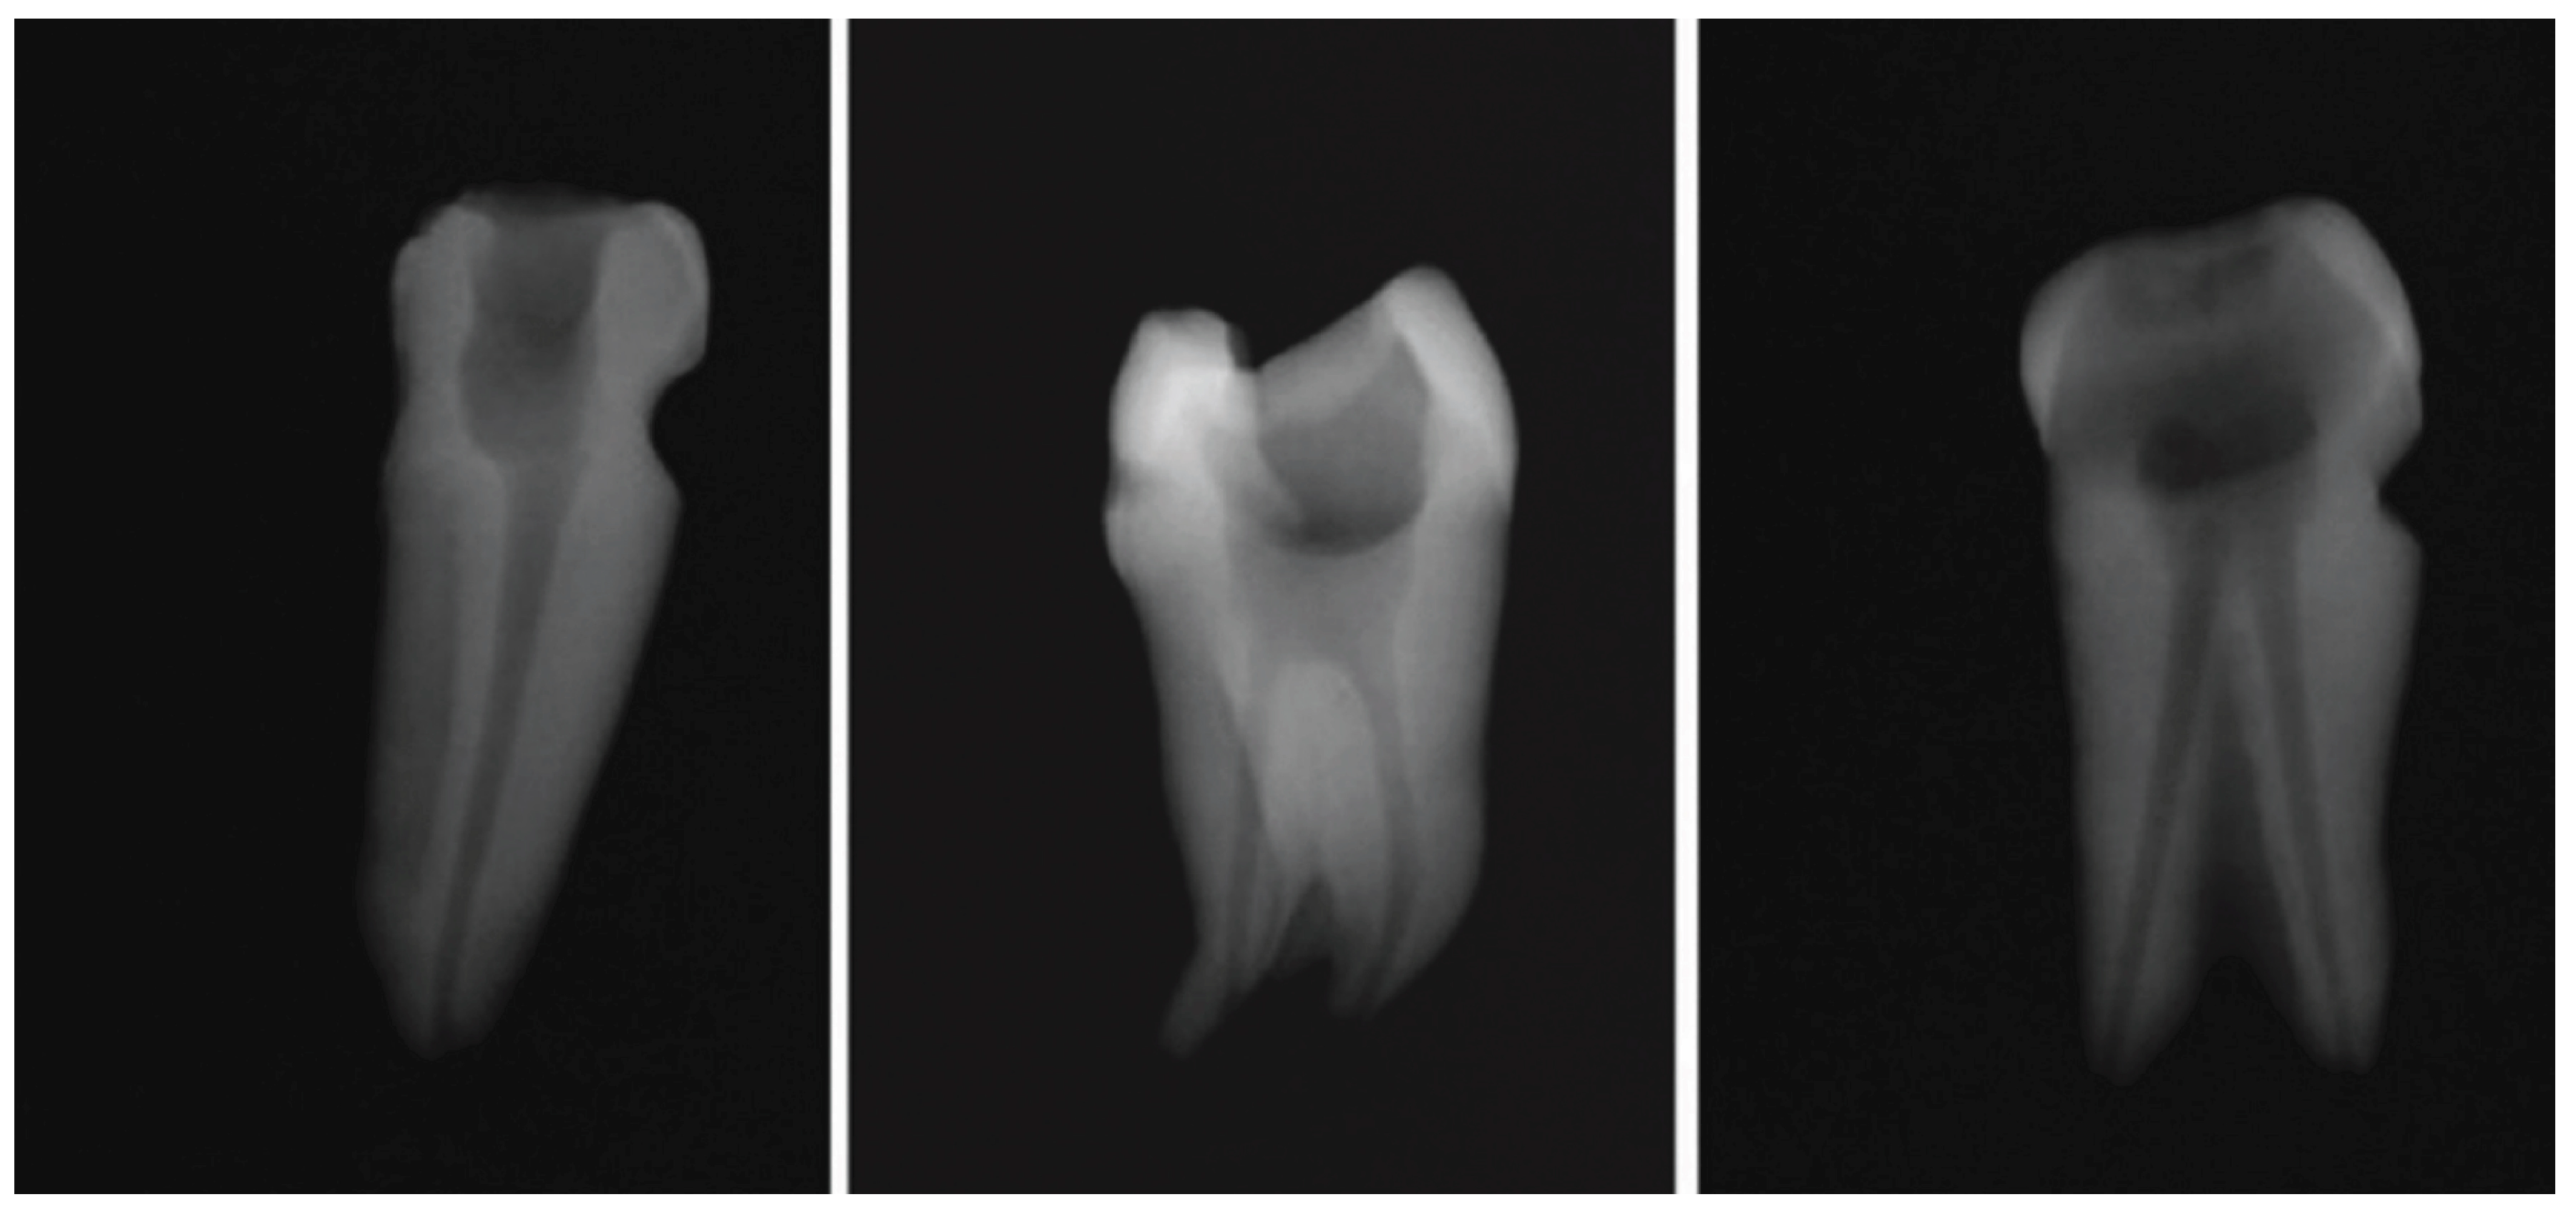

Within dentistry, the OCT system proves adept at diagnosing a range of caries, including occlusal, proximal, and cervical caries. Its utility extends to the comparison of various adhesive materials concerning gap formations beneath composite restorations. Moreover, OCT is instrumental in identifying enamel cracks, vertical root fractures, and cracks within dental composite materials. OCT’s primary benefit in dentistry is its capacity to non-invasively and accurately detect and characterize small defects in dental tissues, materials, and structures. This includes identifying additional canals, isthmuses, recesses, or intra-radicular connections (Figure 1) [14,15,16].

Figure 1. Initial radiographs of select samples following traditional endodontic treatment [15].